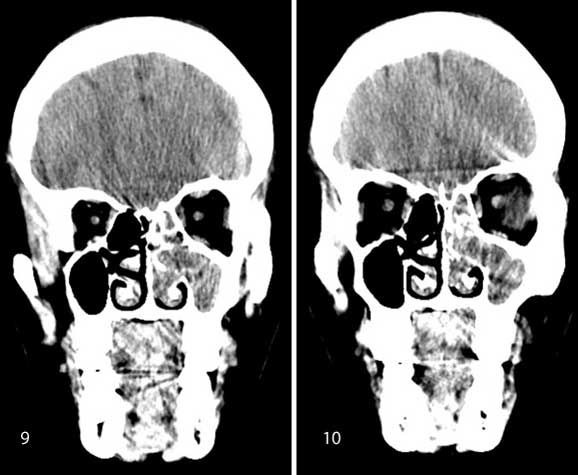

Case history: A 35-year-old patient with history of unilateral nasal obstruction.